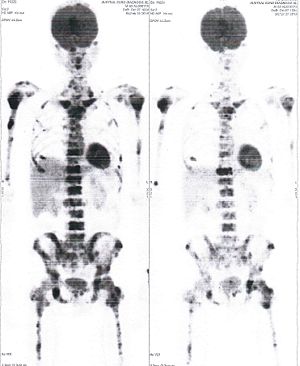

CASE NO: 3 (PROSTATE CANCER)

A middle-aged man with castration resistant prostate cancer, having failed all currently available cancer treatment, was very weak, and getting worse every day. The PET/CT scan showed he had massive bone metastases. After a few treatment, all the bone metastases went into remission. About 6 months later, he is still in remission.